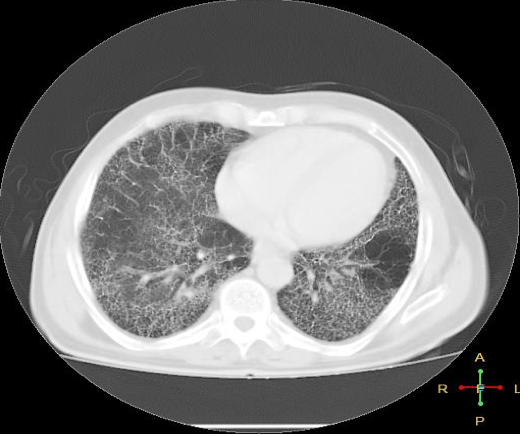

What is this HRCT showing?

What is it indicative of?

HONEYCOMBING indicative of pulmonary fibrosis